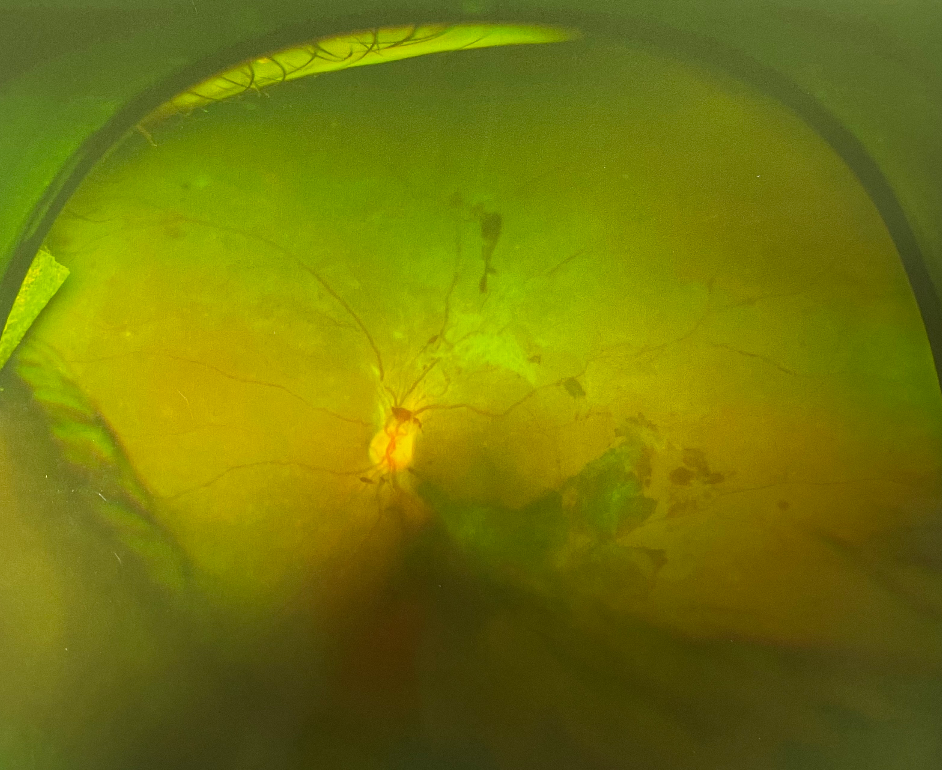

人眼的視網(wǎng)膜血管和脈絡(luò)膜血管系統(tǒng)保障供應(yīng)眼睛能量,并帶走其代謝產(chǎn)物。因此無論這些血管的哪一部分出問題,都會影響視網(wǎng)膜的功能。眼底出血是指血液溢出血管到視網(wǎng)膜內(nèi)或周圍,若其范圍大或位于黃斑部則嚴重影響視力。這種出血需醫(yī)生通過眼底檢查方可看見,一般人是無法看到的。眼底出血是眼科常見病,既可見于老年又可見于青少年,男女均會患病。

眼底出血多因高血壓、糖尿病、視網(wǎng)膜血管阻塞或免疫功能異常引起,常見于高血壓視網(wǎng)膜病變、糖尿病視網(wǎng)膜病變、視網(wǎng)膜靜脈阻塞,視網(wǎng)膜靜脈周圍炎性病變。

眼底出血是老年人的常見病,但常常被忽視,原因是其不易被發(fā)現(xiàn),在外觀上看不出來,只能在醫(yī)院眼底鏡下被檢查出來。老年人易出現(xiàn)眼底出血,原因是老人的血管柔韌性和彈性發(fā)生改變,較硬且脆,稍有刺激便可能出血。伴高血壓、糖尿病、動脈硬化、高脂血癥的病人,眼底血管硬化,應(yīng)特別注意。

眼底出血發(fā)生后病情的發(fā)展并非靜止不變,若未經(jīng)及時有效治療,出血不斷流人玻璃體腔,會導(dǎo)致玻璃體積血。出血停止后可通過自身的吸收功能將其吸收。出血量少,自身吸收功能好則可痊愈,反之溢出血管的血液成分會引發(fā)視網(wǎng)膜玻璃體的增殖,還會破壞周圍組織,造成視網(wǎng)膜缺氧,誘發(fā)新生血管等,從而引發(fā)嚴重并發(fā)癥——新生血管性青光眼,牽位性視網(wǎng)膜脫離等。所以發(fā)生眼底出血要盡早就醫(yī)。